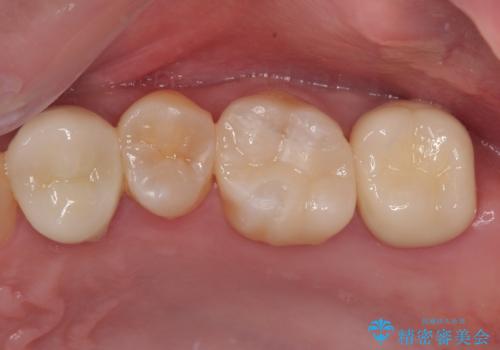

奥歯の大きなむし歯 神経を残してセラミック治療